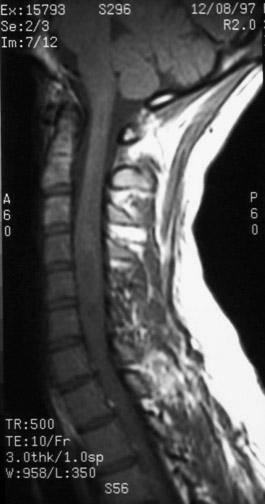

Что такое эпендимома спинного мозга: симптомы и лечение